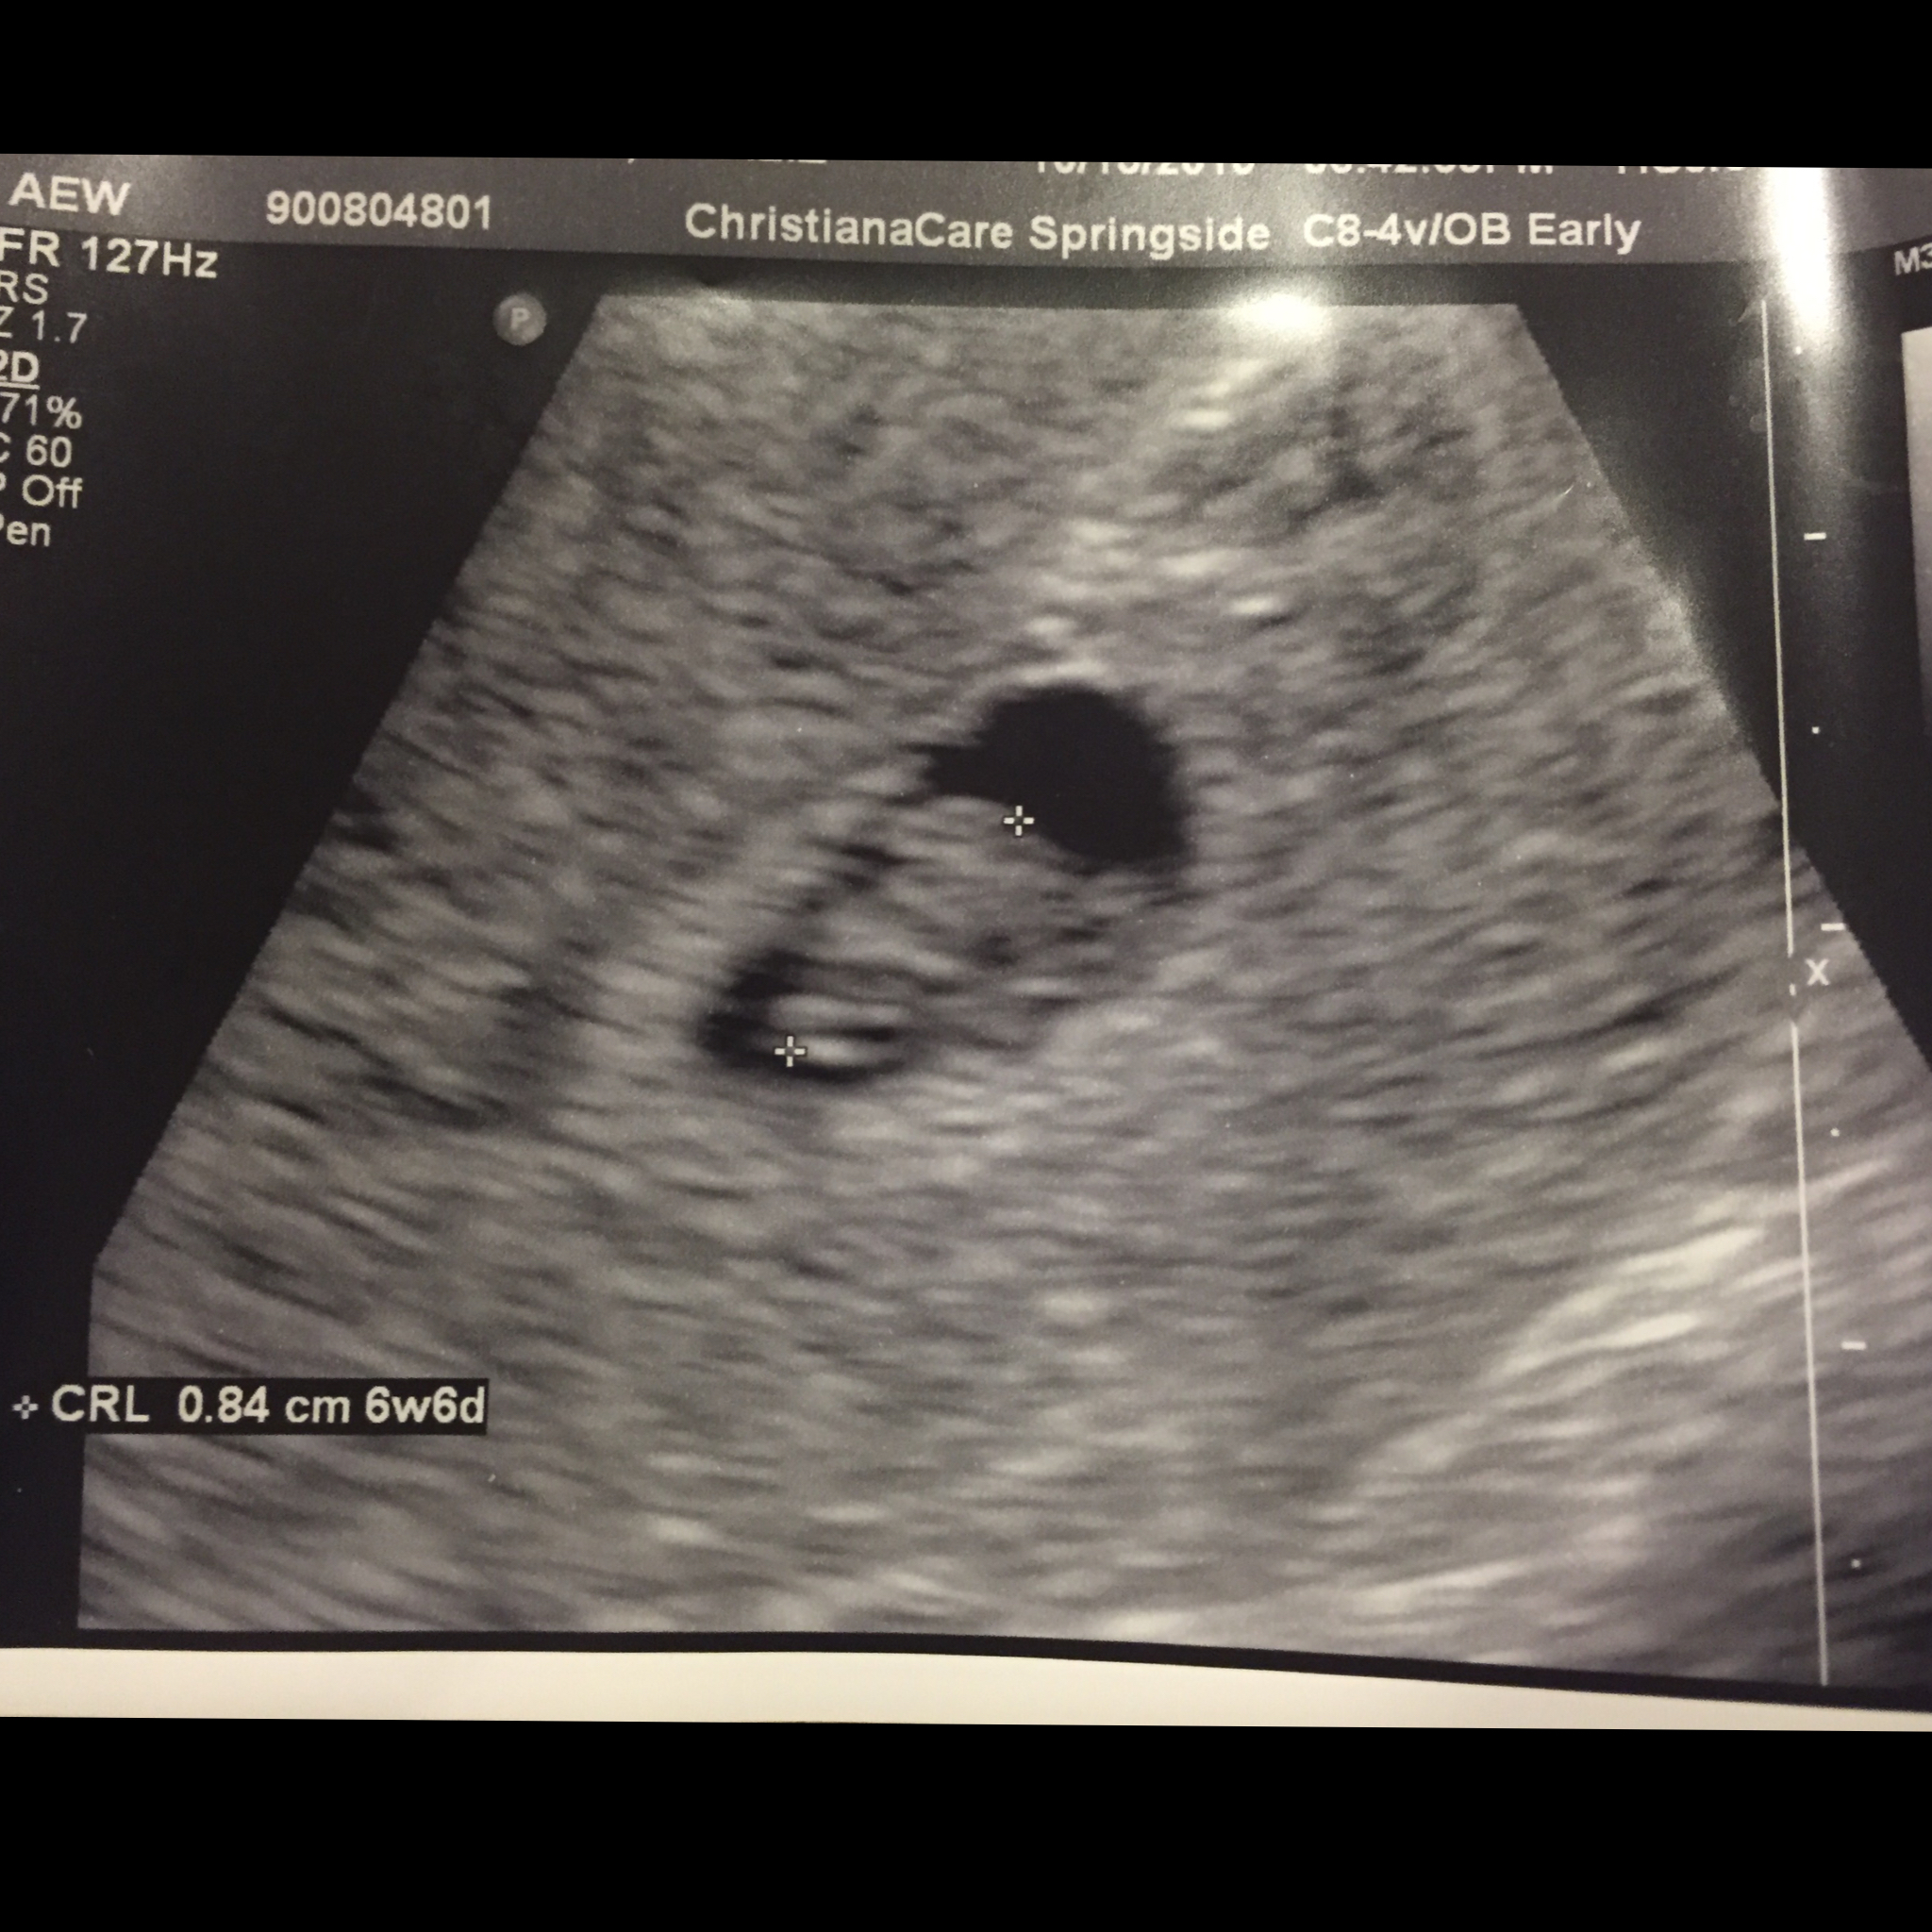

• I just went last night to the ER and was able to see my little baby at 6 weeks and 3 days. We even saw the flicker of the heart. Amazing!

Had one today at 5w 4d. She saw a sack with a yolk and a fetal pole. Beginning of a flicker of a heartbeat, hopefully it will be good and strong at our appt. next week at 6w 5d.